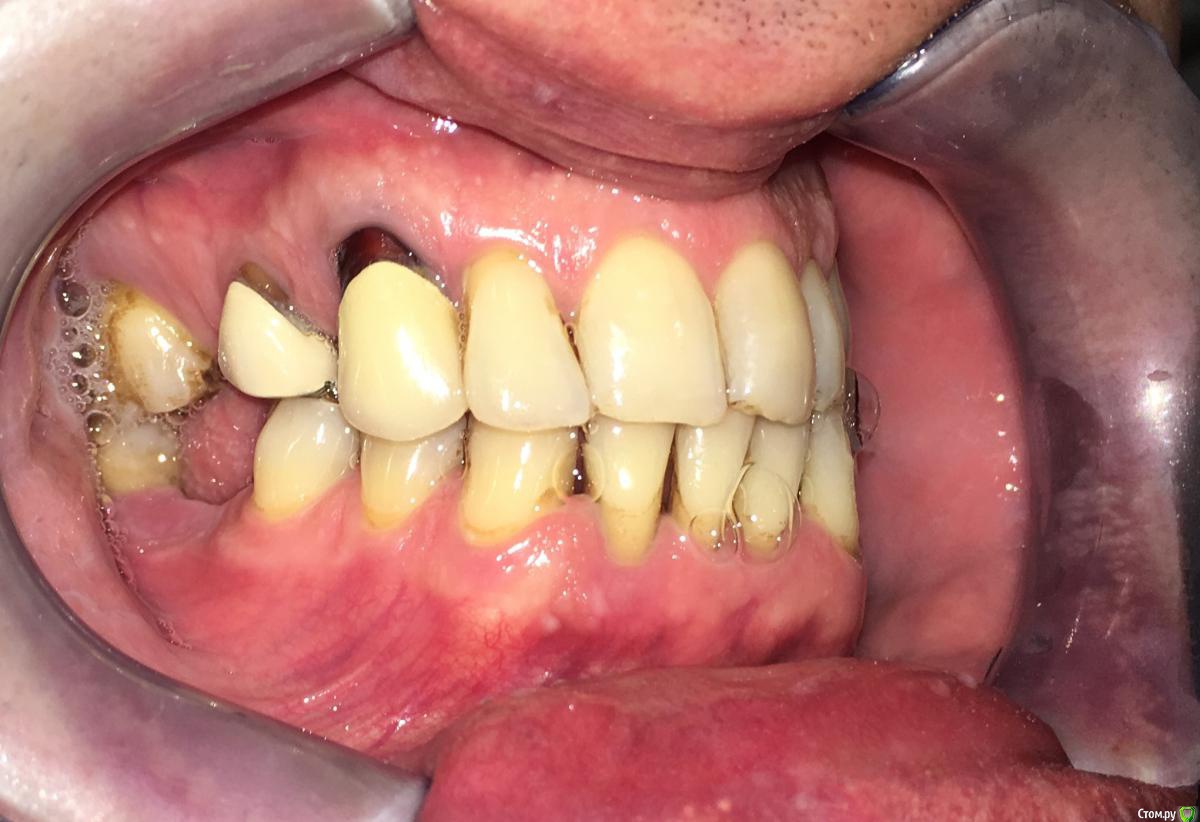

Nitrino1 Опубликовано 20 января, 2018 Поделиться Опубликовано 20 января, 2018 Коллеги помогите поставить правильный диагноз и составить план лечения, чтоб продолжительно держалосьОбъективно на всех зубах камни над и поддесневые. В 47ом зубе 3-я степень подвижность.Почистил все камни и налеты, назначил полоскание, пасту Парадонтах, удалил 47ой зуб.Сделал панорамку (до удаления) и фотки тоже до удаления.Должен составить план лечения... Ссылка на комментарий

Nitrino1 Опубликовано 21 января, 2018 Автор Поделиться Опубликовано 21 января, 2018 Хронический генерализованный пародонтит тяжелой степени, в ремиссии (по МКБ-10 Хронический генерализованный пародонтит, код К0531)какой план лечения вы бы порекомендовали? интересует момент с нижними резцами, их шинировать или же удалить? на верхних 6ках тоже ситуация не очень. Вообще какую тактику выбрали бы?И еще просьба, посоветуйте что можно почитать современное на тему парадонтитов и парадонтозов, то что у меня есть это старое уже Ссылка на комментарий

almaz7888 Опубликовано 3 февраля, 2018 Поделиться Опубликовано 3 февраля, 2018 Шинирование нижних резцов в связке с соседними зубами после предварительно го депульпирования зубов. В последующем лоскутная операция. Избирательное пришлифовывание. 1 3 Ссылка на комментарий

chervoncevdaniil Опубликовано 5 февраля, 2018 Поделиться Опубликовано 5 февраля, 2018 (изменено) Удалить подвижное+гигена/кюретаж+остальные коронки+кламмерный бюгель.Сейчас вам могут написать про тотальную имплантацию с объемные костными пластиками и т.д,вы конечно это все внимательно прочитайте,пациенту обязательно предложите и посчитайте приблизительную стоимость,огласите сроки и если вдруг окажется(ну мало ли ),что к такому протезированию он не готов,обсудите вариант с бюгелем,пусть даже как временный,чтобы он собирал деньги на имплантацию в перспективе(но по опыту этот вариант окажется и постоянным) Изменено 5 февраля, 2018 пользователем chervoncevdaniil 1 Ссылка на комментарий

Nitrino1 Опубликовано 13 февраля, 2018 Автор Поделиться Опубликовано 13 февраля, 2018 Удалить подвижное+гигена/кюретаж+остальные коронки+кламмерный бюгель.Сейчас вам могут написать про тотальную имплантацию с объемные костными пластиками и т.д,вы конечно это все внимательно прочитайте,пациенту обязательно предложите и посчитайте приблизительную стоимость,огласите сроки и если вдруг окажется(ну мало ли ),что к такому протезированию он не готов,обсудите вариант с бюгелем,пусть даже как временный,чтобы он собирал деньги на имплантацию в перспективе(но по опыту этот вариант окажется и постоянным)Пока что шинировал фронтальные подвижные зубы с помощью ретейнера. Пока наблюдаю и переделываю коронки) тотальную имплантацию не предлагаю)) Ссылка на комментарий